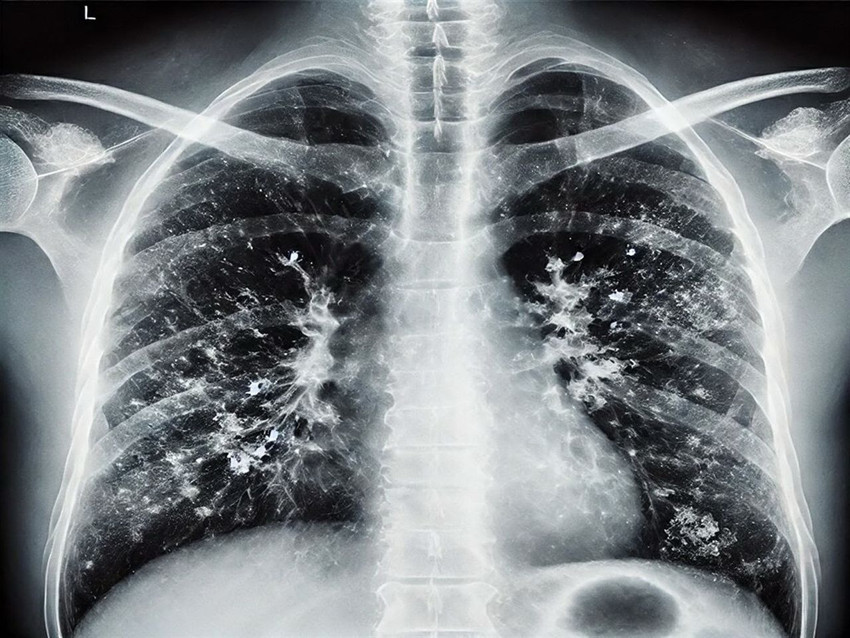

Gribal enfeksiyonlar açısından influenzada ciddi bir yükseliş olduğunu ifade eden Prof. Dr. Şener, "İnfluenza dışında RSV ve rinovirüs de görülüyor. Gribal enfeksiyon geçirdikten sonra bakteriyel enfeksiyonlar, süperenfeksiyon olarak ortaya çıkıyor. Bu süperenfeksiyonlar, bakteriyel olduğunda bazen ağır tablolara neden olabiliyor. Zatürre, pnömoni, akciğer iltihabı gibi durumlar hastaneye yatışa hatta oksijen desteği ihtiyacına sebep olabilecek klinik tablolara yol açabiliyor. Bu açıdan dikkat etmek lazım. Aile hekimine başvurduğunuzda ücretsiz grip aşınızı olabilirsiniz" dedi.

Özellikle 65 yaş üstü vatandaşlara yönelik uyarılarda bulunan Prof. Dr. Şener, "Bu grupta RSV dediğimiz viral enfeksiyon önem taşıyor. RSV, akciğerde yaygın enflamatuar tabloya sebep oluyor. Bunun da aşısı var. Cebinizden ücret ödeyerek yaptırabileceğiniz bir aşı. Özellikle 75 yaş üstü bireylerin mutlaka olması gerekiyor. 65 yaş üstünden başlarsak viral enfeksiyonlar ağır seyrediyor. Koronavirüs döneminde bunlara alışkındık; pandemi sonrasında da ağır viral enfeksiyon tablolarıyla karşı karşıya kalmaya başladık. Ciddi solunum yetmezliği, ateş, üşüme ve titreme semptomları; acil servise başvuru ve oksijen desteğine rağmen toparlanamama gibi durumlar görüyoruz. Bu nedenle bu hastalar, bazen normal servise bazen de yoğun bakıma yatmak zorunda kalıyor. Bu hastalar maalesef bazen her türlü tedaviye rağmen akciğerdeki ağır enfeksiyonun yaygınlaşmasıyla ölüme kadar ilerleyebilen klinik tablolara sebep olabiliyorlar" diye konuştu.